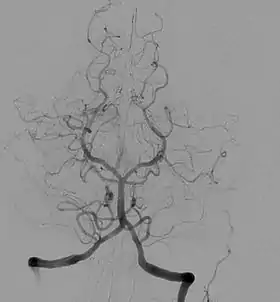

تَصْويرُ الأَوعِيَة أو تصوير الشرايين (بالإنجليزية: Angiography) هو تقنية تصوير طبية تُستخدم لتصور الأوعية الدموية وأعضاء الجسم من الداخل أو التجويف، مع الاهتمام بشكل خاص بالشرايين والأوردة وغرف القلب. يتم ذلك عادةً عن طريق حقن عامل تباين غير شفاف في الأوعية الدموية والتصوير باستخدام تقنيات تعتمد على الأشعة السينية مثل التنظير الفلوري.

إجراء تصوير وعائي شائع آخر بشكل متزايد هو الأوعية الدموية العصبية بواسطة تصوير الأوعية بالطرح الرقمي [الإنجليزية] من أجل تصور الإمداد الشرياني والوريدي للدماغ. العمل تدخل مثل لفائف الانصمام من تمدد الأوعية الدموية و التشوهات الشريانية الوريدية يمكن أيضًا إجراء عملية الإلتصاق.